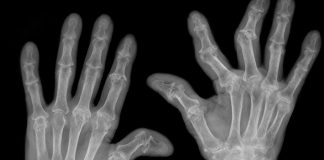

Artrite reumatoide: stimolare il nervo vago riduce l’infiammazione

Artrite reumatoide: patologie sistemiche oltre le articolazioni